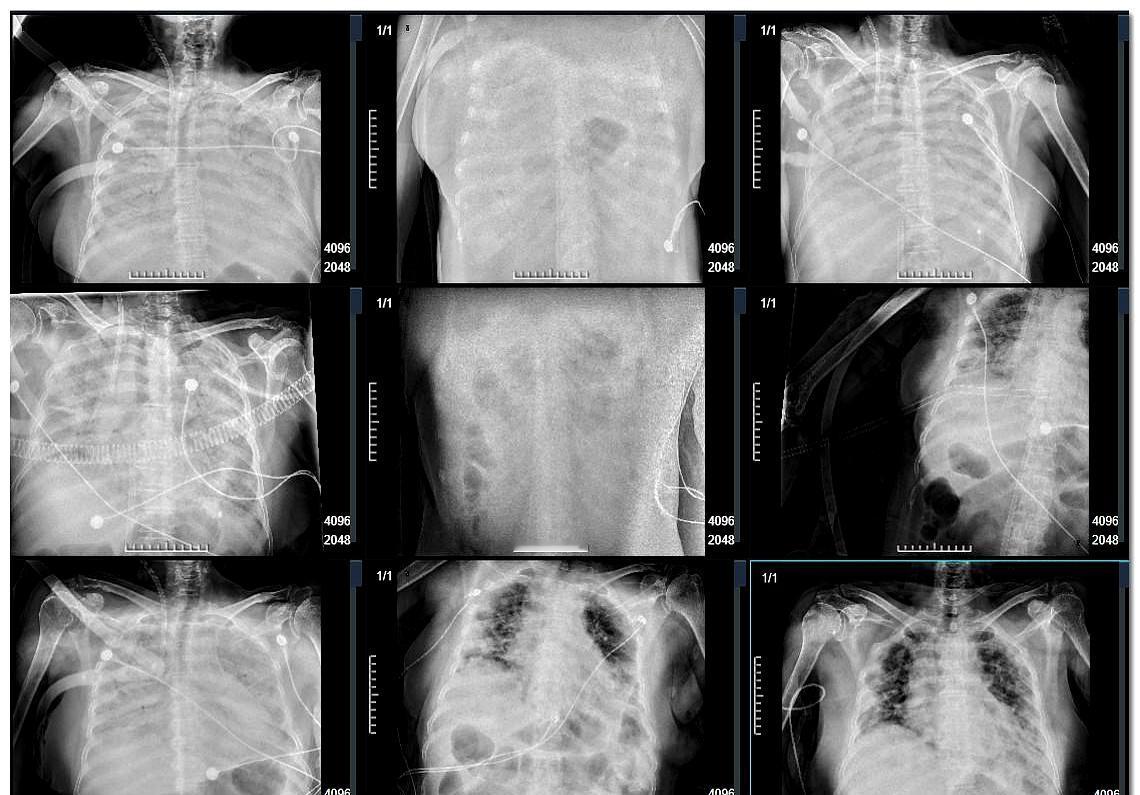

从医这么多年,真没见过比这更凶险的病 晚期肺癌在它面前,都算是个“善终”了 年前接诊一个病人,能走能动,就是肺有点问题,看着还行。 但化验单上一个叫“MDA5抗体”的东西,强阳性,我一看头皮都麻了,心里咯噔一下 这玩意儿就是个“死亡信号”,我没敢瞒着,直接跟家属说,做好心理准备,一个礼拜,人可能就不行了 家属当时还半信半疑,觉得我危言耸听。 结果,一天一个样,真就一个礼拜,肺全白了,跟毛玻璃似的,呼吸机都没用,心肝肾功能也跟着往下掉,各种好药砸进去,连个响都听不到 最后只能上ECMO,也就是俗称的“人工肺”,用机器硬吊着一口气,等着看有没有肺移植的机会 说实话,这比喝农药还快,根本不给人反应时间。 当医生越久,越觉得人类在疾病面前,真是太渺小了